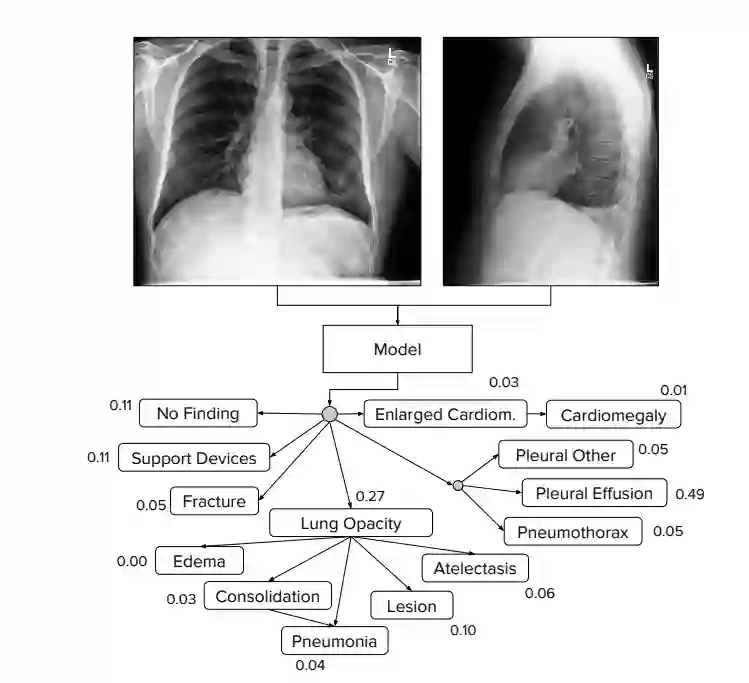

图:CheXpert 任务是预测来自多视图胸片的不同观察结果的概率。